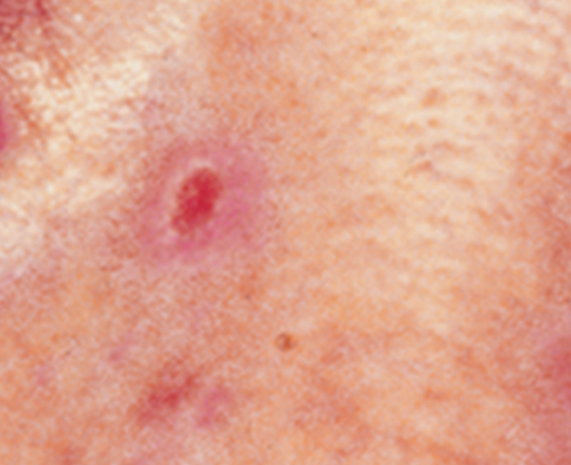

An elevated growth with a central depression that occasionally bleeds. It may rapidly increase in size. (SCC)

Squamous cell carcinoma on the nose. Photo: International Skin Imaging Collaboration at isic-archive.com